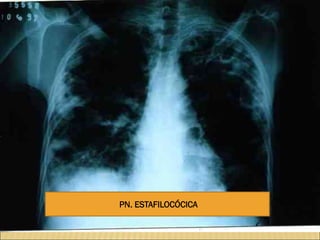

PN. ESTAFILOCÓCICA